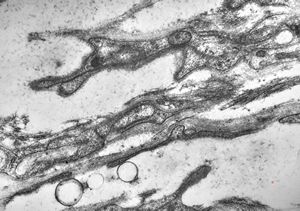

rabbit spinal cord trauma

rabbit spinal cord trauma